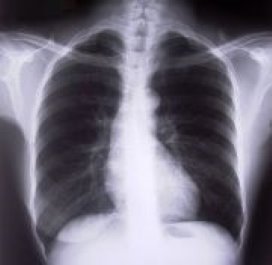

Kwaadaardige longvlekjes beter te onderscheiden

Nederlandse en Belgische artsen hebben een nieuwe methode ontwikkeld waarmee op een eenvoudige manier en met grote nauwkeurigheid kwaadaardige vlekjes in de longen kunnen worden onderscheiden van goedaardige vlekjes.

De nieuwe methode voorkomt veel